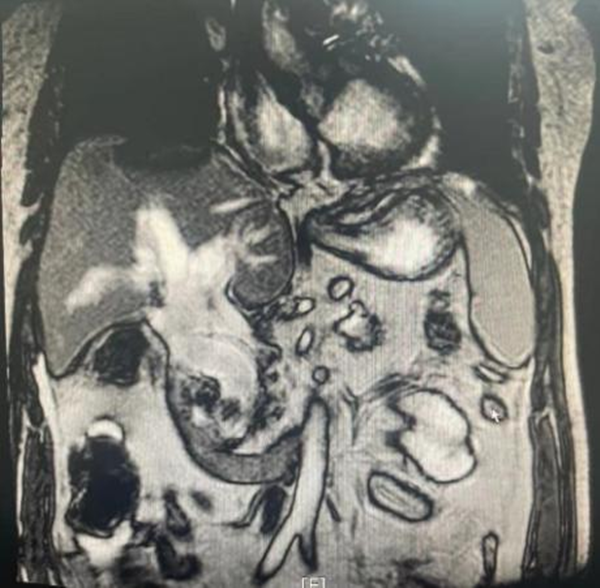

干四(普外四病区)收住一名70岁老年男性梗阻性黄疸患者,患者入院前已经反复高烧两周,多年前做过开腹胆囊切除,胆总管探查手术。肝功显示重度黄疸,合并急性肾功能不全,少尿,肌酐最高达700umol/L。患者年龄大,肝肾功差,如果采取开腹手术系二次胆道手术,难度和风险都很大。入院后虽然第一时间在彩超引导下放置了经皮经肝胆管引流,但引流液过于浓稠,退黄效果不佳,感染逐渐加重,出现了低体温,神志淡漠的休克表现。核磁共振检查显示胆管被直径约2cm的巨大结石完全堵死,胆管内充满高密度物质,病情危重。

干四病区(普外四病区)王志东副主任医师、蒋安副主任医师、黎跃华主治医师快速评估病情后认为患者系急性化脓性梗阻性胆管炎(重症胆管炎)、胆总管结石,合并多器官功能障碍,有休克表现,生命体征不稳,手术风险很大,术后需进入ICU,花费不少。急诊行微创ERCP取石,引流脓液是最好的选择。在消化内科李婵主管护师的安排下,由蒋安副主任医师主刀、梁金强医师密切配合急诊行ERCP手术,发现患者十二指肠乳头开口于肠憩室内,属于较困难的插管类型,但经过短时间调整后插管成功。造影发现胆总管宽约3cm,胆总管内充满粘稠的脓性胆汁,被巨大结石堵塞,单纯引流效果不佳。遂决定尝试尽可能一期取石以解除梗阻,因结石较大难以完整取出,所以先在胆管内将结石破碎,再逐块取出。浓稠的脓液也通过网篮逐步脱出。手术完成后,患者感染迅速控制,未再发烧,黄疸迅速下降,在肾内科会诊治疗下肾功能及精神状态明显改善,目前生命体征良好。